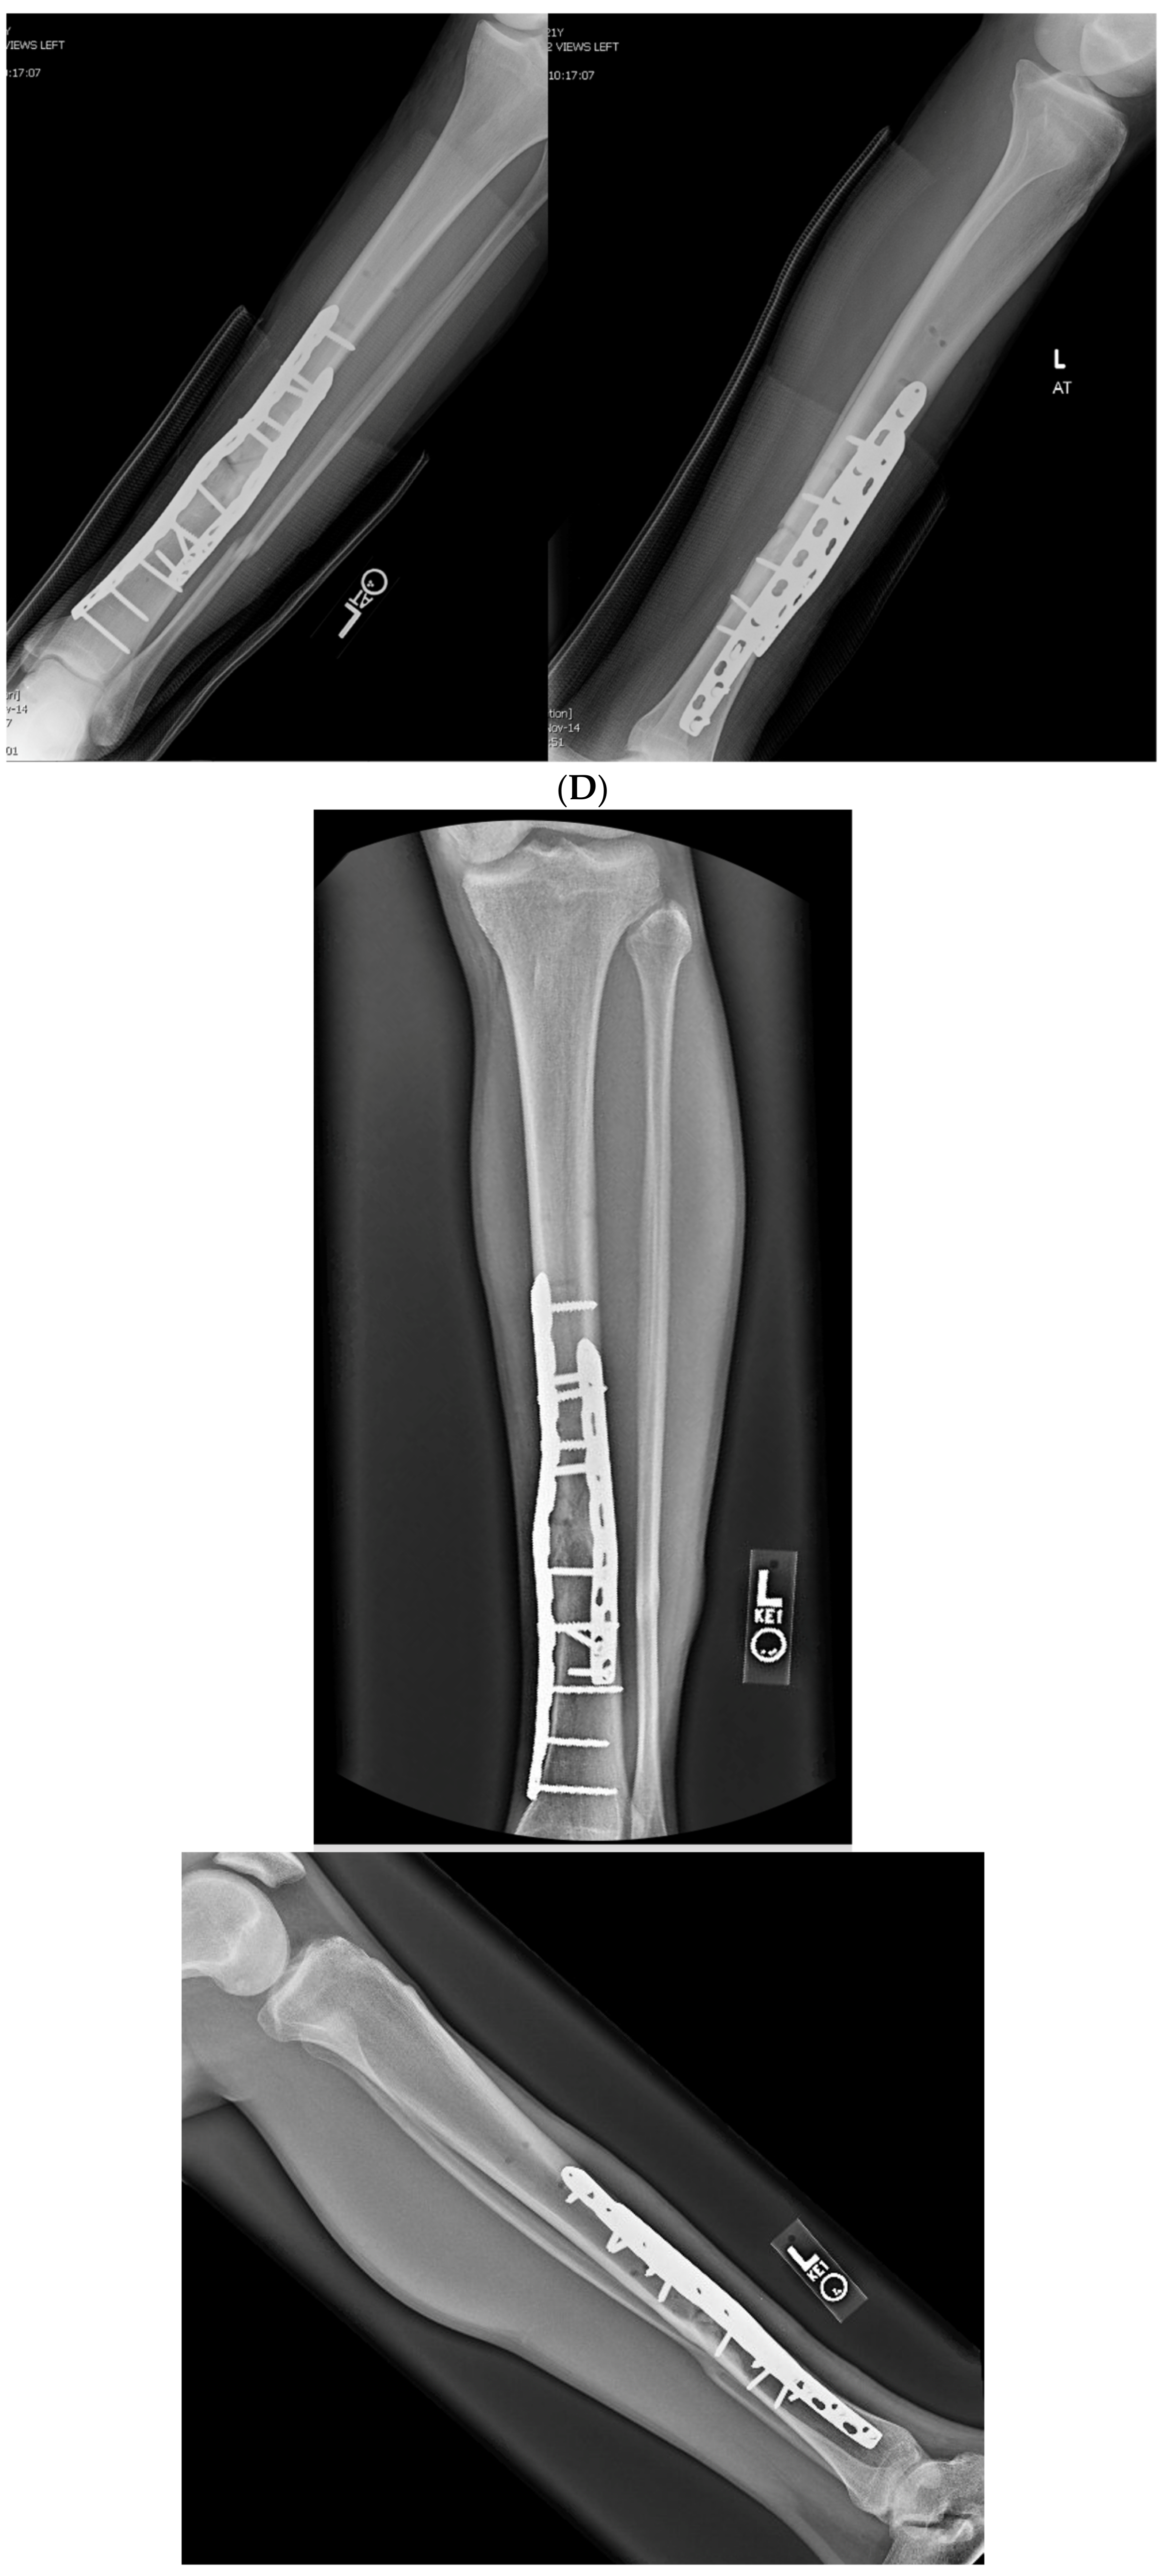

3.2. Case 2-Single-Plane Correction with Plate Fixation: Tibia

A young adult college baseball player presented with symptoms of lateral proximal knee pain and a feeling of knee instability 8 months after sustaining a closed fracture of the tibia, initially treated closed with casting (Figure 7A). The patient underwent a workup including full-length films, knee MRI, and local anesthetic test injection of the proximal tibiofibular joint (relieving knee pain). The CORA analysis revealed a recurvatum deformity of 10 degrees and varus deformity of 3 degrees, with translation in the coronal plane. Full-length alignment film of the pelvis and lower extremity confirmed coronal translation with mild varus angulation (Figure 7B). The true plane of deformity was calculated approximately 75 degrees from the coronal plane (15 degrees off-sagittal) with a magnitude of between 10 and 11 degrees.

Figure 7.

(A) A young adult college baseball player sustained a closed tibia fracture with intact fibula, treated closed. The patient developed a recurvatum deformity with pain at the proximal and distal tibiofibular joints. (B) The patient demonstrated mechanical axis lateralization due to coronal plane translation with slight varus. The plane of deformity was calculated as 73 degrees off of the coronal plane. (C) The patient underwent focal dome osteotomy at the CORA (yellow circle) in the plane of maximum deformity. (D) Dual plate compression was used. Angulation and translation were simultaneously corrected. (E) Final follow-up 9 months: anteroposterior, lateral, and oblique films show the osteotomy healed. Tibiofibular joint pain resolved after osteotomy. Patient returned to college-level baseball.

A focal dome was chosen to correct the varus recurvatum and translation. The surgical approach was an anterior approach over the anterior compartment, elevating the tibialis anterior from the lateral tibia to allow safe access to the plane of the deformity. The fibula was osteotomized near the level of the tibia through a separate lateral approach. The plane of maximum deformity was assessed intraoperatively and confirmed the preoperative calculations. The ‘no deformity’ view on fluoroscopy was located, with the maximum plane orthogonal to this. It is in this plane that the drill bit at the CORA is directed, and this is especially important if correcting a translation. The arc of the osteotomy was drawn using a parallel drill guide with one bit centered at the CORA (Figure 7C).

The angulation and translation were simultaneously corrected. Dual medial–lateral plates were used to counteract the lateral gap forming with medial plate compression. Hence, balanced compression from the medial and lateral plates restored the alignment and provided absolute stability (Figure 7D). The patient had immediate relief of knee pain after correction. The soft tissue and osteotomy healed without incident (Figure 7E).